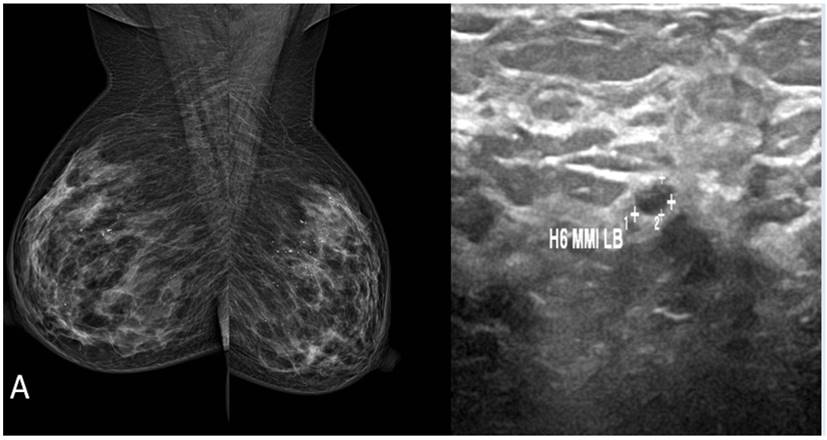

Figura 2. Tejido mamario heterogéneamente denso ACR C. A.), Mamografía Proyección media oblicua lateral B. Ecografía de mama izquierda. BIRADS 2

En la ecografía mamaria. BIRADS0, adenopatía axilar derecha a nivel I. informa de mamografía indica tejido mamario heterogéneamente denso ACR C. La densidad mamaria no permite la identificación de lesiones nodulares, ni lesiones no nodulares. Se realiza resonancia magnética de mama, evidenciando lesión estelar de 17x15 mm localizada en la unión de los cuadrantes internos de mama izquierda. Por lo cual se realiza second look ecográfico y se biopsia lesión ecoguiada de lesión mamaria izquierda y además aspiración de lesión ganglionar derecha. Con reporte de carcinoma invasor lobulillar infiltrante de mama positivo al receptor de estrógeno, positivo al receptor de progesterona, Her 2 negativo, cadherina negativa, k-67 expresión nuclear en el 15 % de las células. Paciente en contexto de Cáncer de mama, premenopáusica, se realizará supresión ovárica para posteriormente tratamiento hormonal.

La búsqueda del tumor primario clásicamente se realiza a través de la mamografía, sin embargo, la sensibilidad del método, en estos casos varía entre 0 % y 56 %, según lo que reporta la literatura,(10,11) de ahí que varios estudios actuales han demostrado el potencial de la resonancia nuclear magnética (RNM) para detectar lesiones ocultas, con cifras de sensibilidad del método de hasta 85 % a 100 %.(10,12,13)